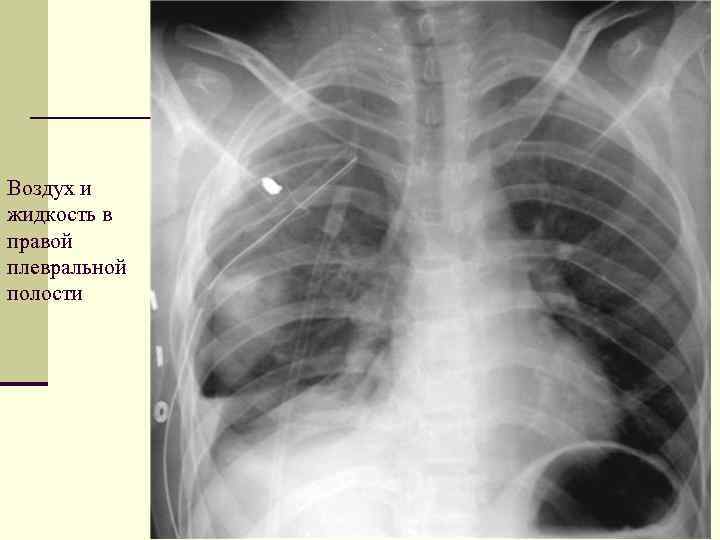

Симптомы и причины скопления воды в легких